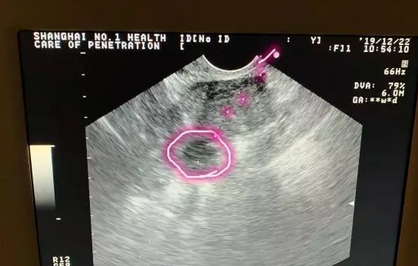

卵巢位置不好则取卵疼痛感强

而这种情况,取卵针要经过子宫,长途跋涉后才能刺入卵泡,那肯定疼,我给你取卵也会疼!